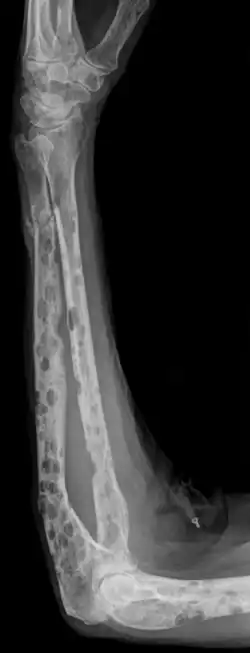

Ostéolyses multiples et fracture pathologique de l'ulna.

La radiographie du squelette montre très fréquemment des lésions osseuses de type ostéolyse.